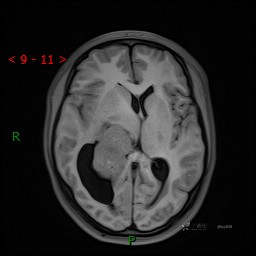

简要病史:患者于1月前无明显诱因出现视物模糊,无明显头痛头晕,无恶心呕吐,无昏迷,无肢体偏瘫等症状,就诊于当地医院头部CT考虑:右侧丘脑、脑室占位。予以对症处置后家属为求进一步诊治来我科,以“颅内占位”收入院。 起病以来,精神、饮食、睡眠欠佳,大小便正常,体力下降,体重无明显变化。

辅助检查:CT MRI

临床诊断:脑室占位

MRI平扫